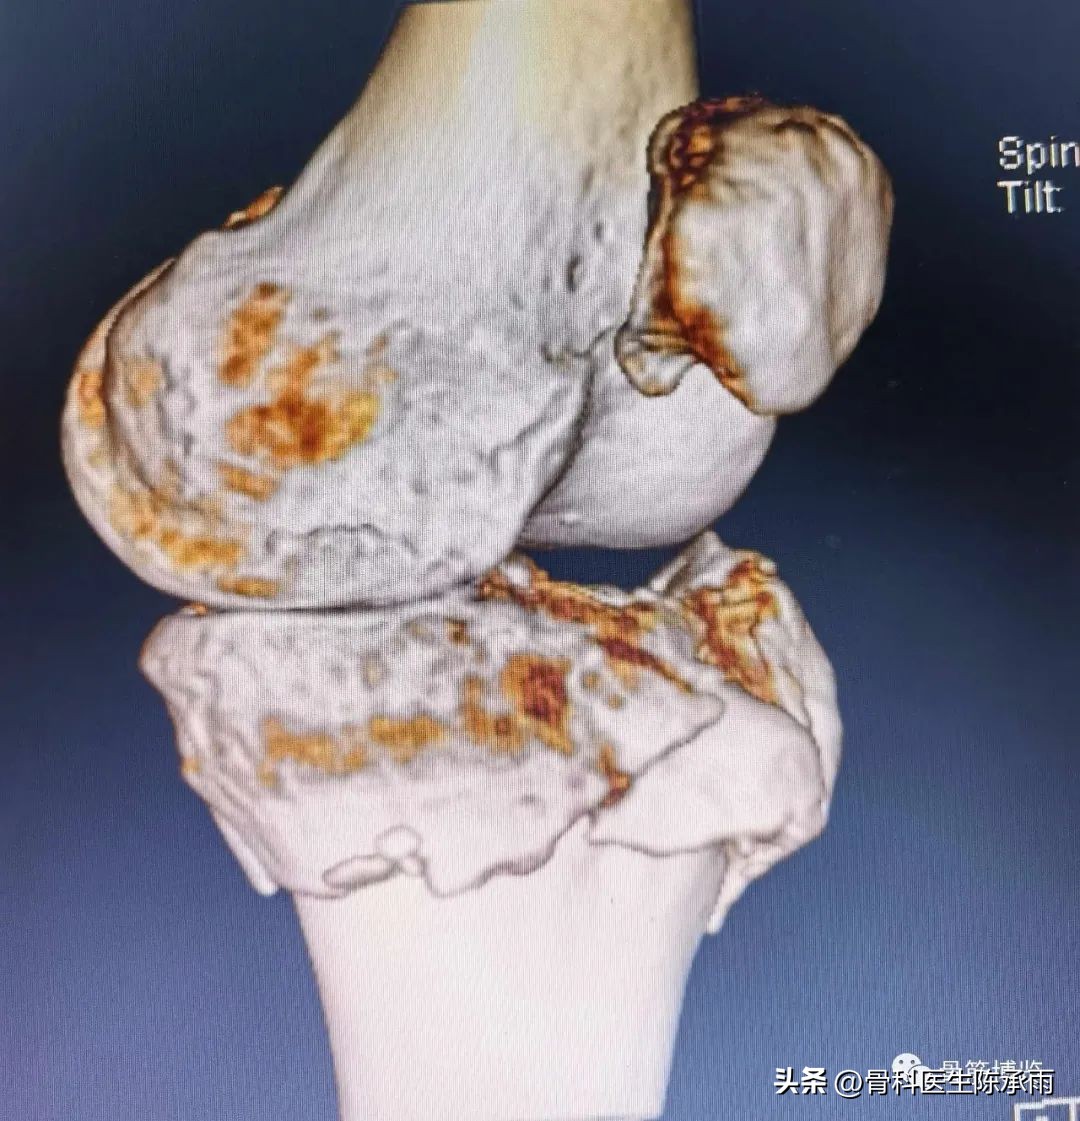

近段时间的胫骨平台骨折,没来得及详细整理

胫骨平台骨折的分型比较多,我们临床上常用的就是Schatzker分型和AO骨折的分型,还有骨折脱位的Hohi-Moore分型,这是我们常用的三个分型。

对AO 分型来讲,现在这是AO推出来更详细的,再分为ABC。随着分型的增加,从A到C骨折的损伤程度是越来越重,治疗也越来越困难,从1到2 ,123也是这个规律,骨折的分型就是给我们表明了骨折的一个损伤的程度,治疗办法和损伤的特点。我们对于骨折脱位的分型,常用Hohi-Moore分型,这个是弥补了,Schatzker和AO分型的一些缺陷。